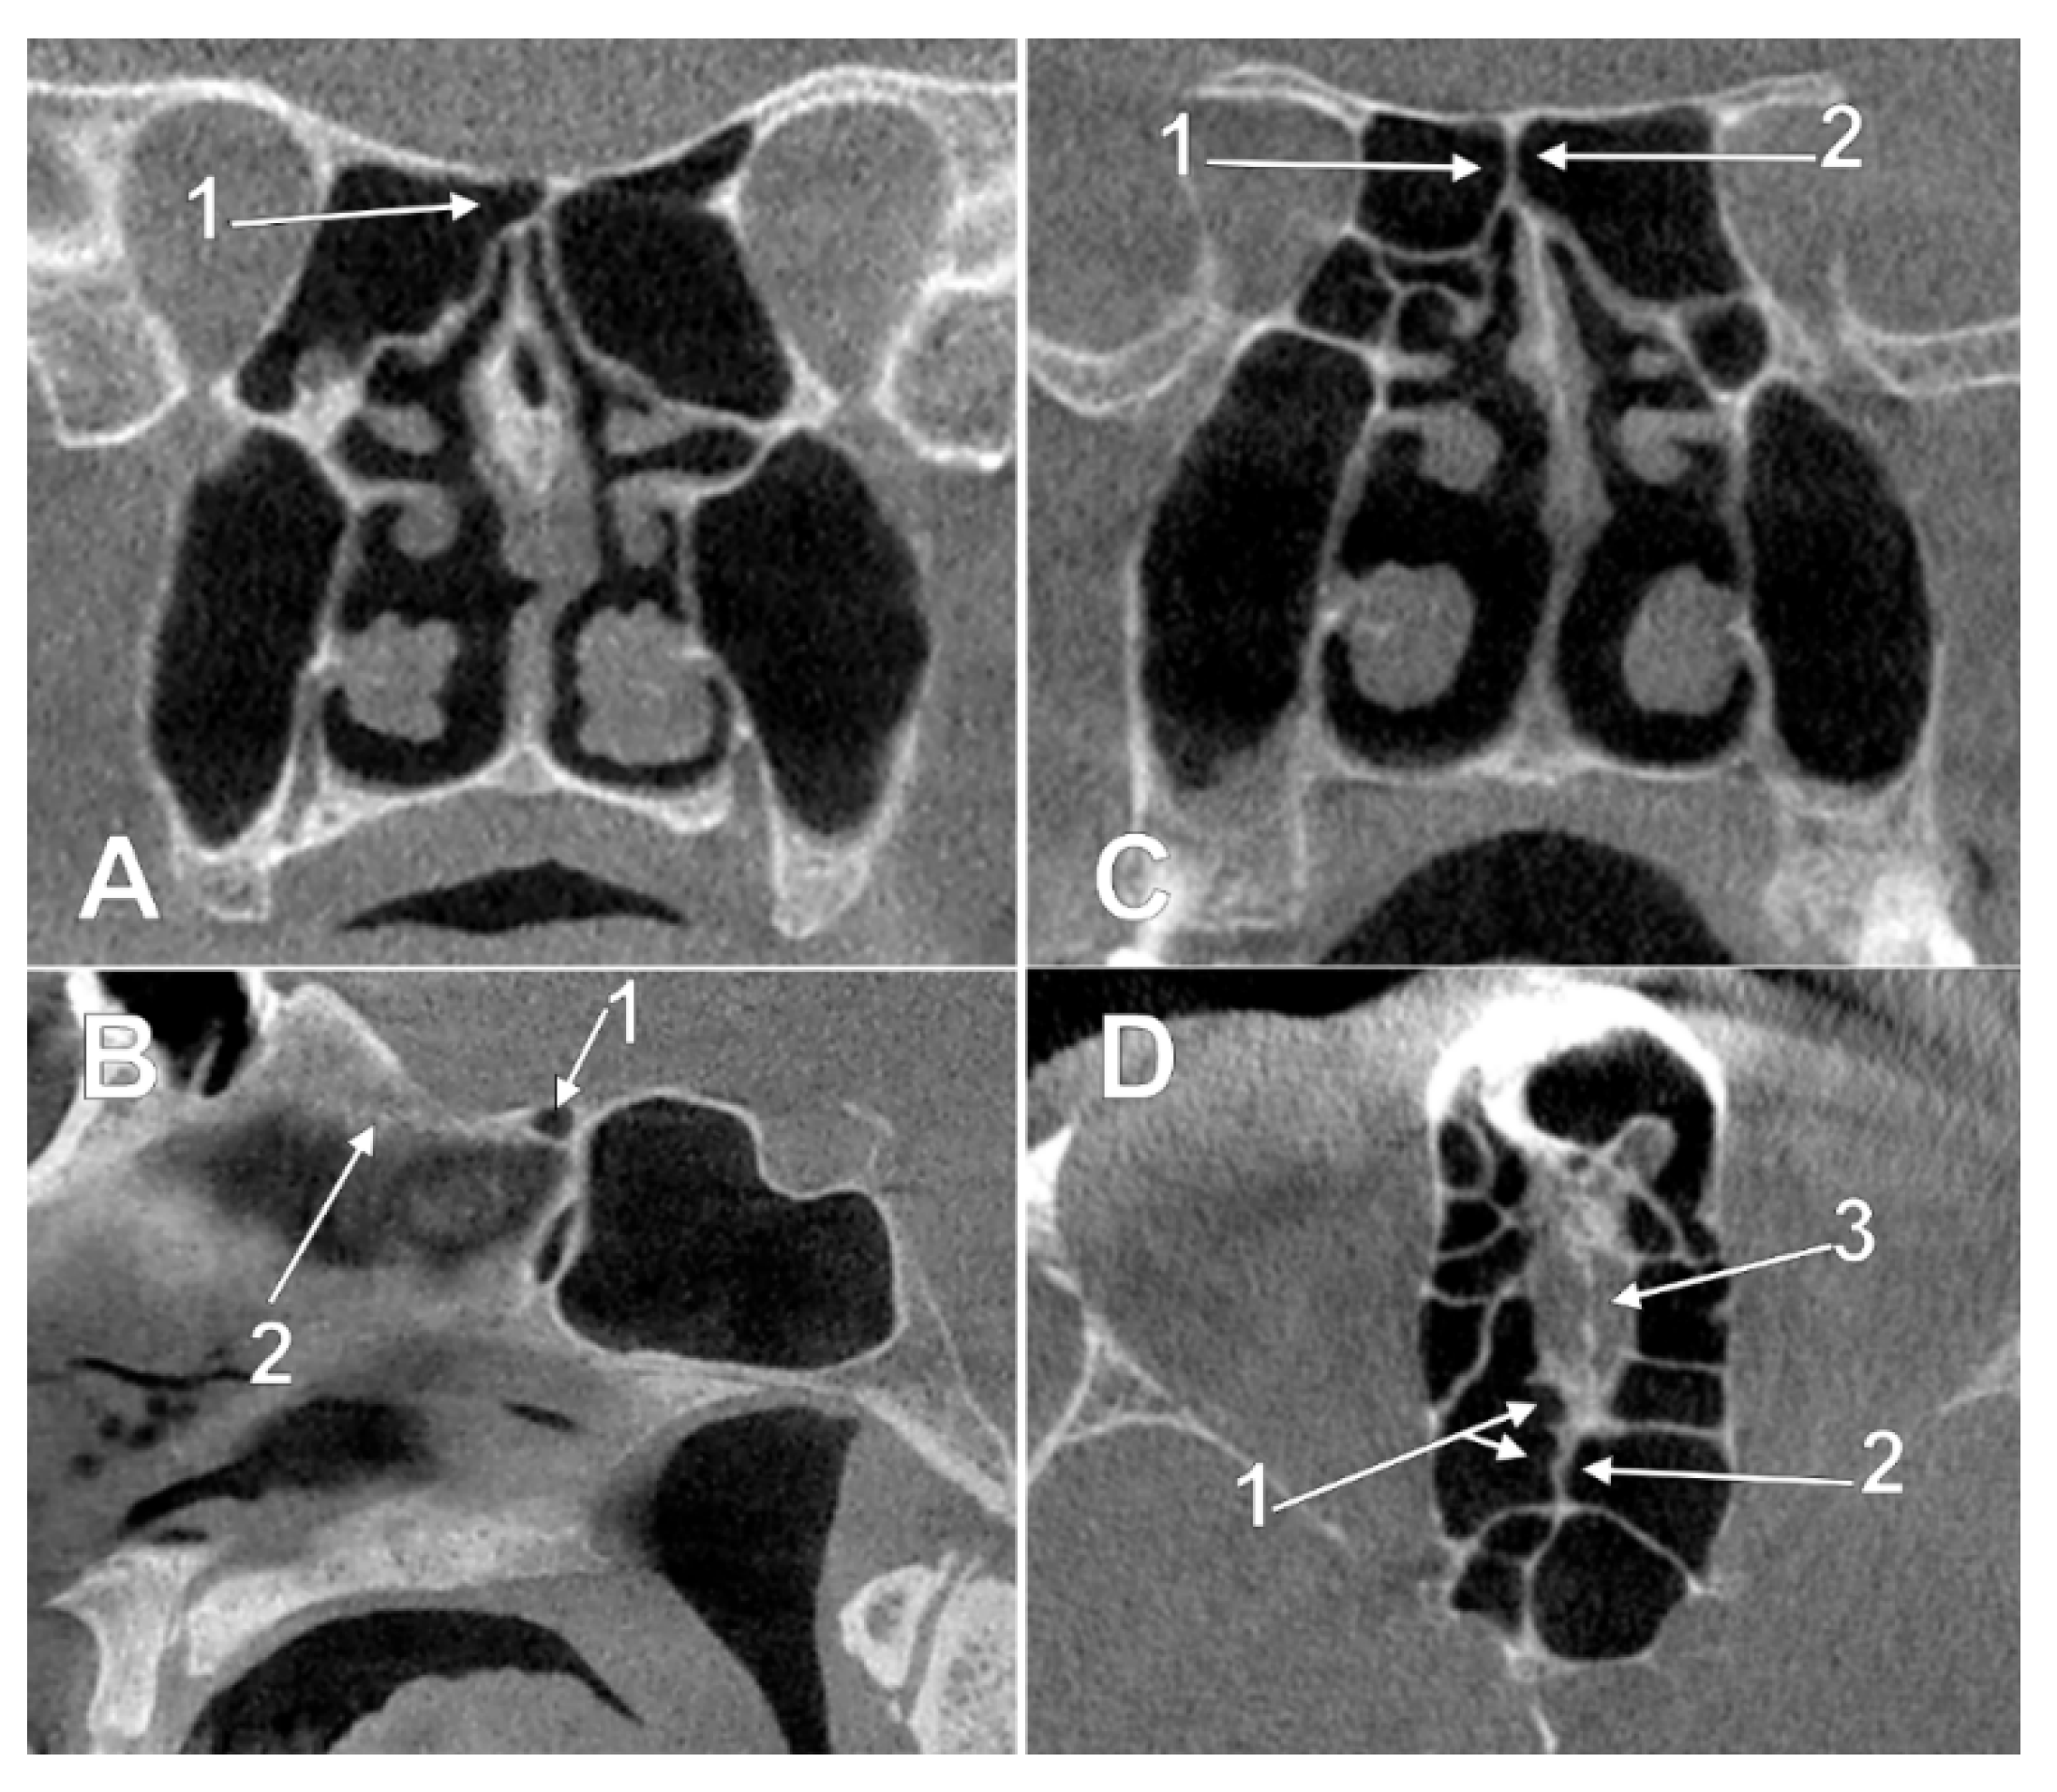

3.1. Ethmoidal Origin of Nasal Roof Pneumatizations